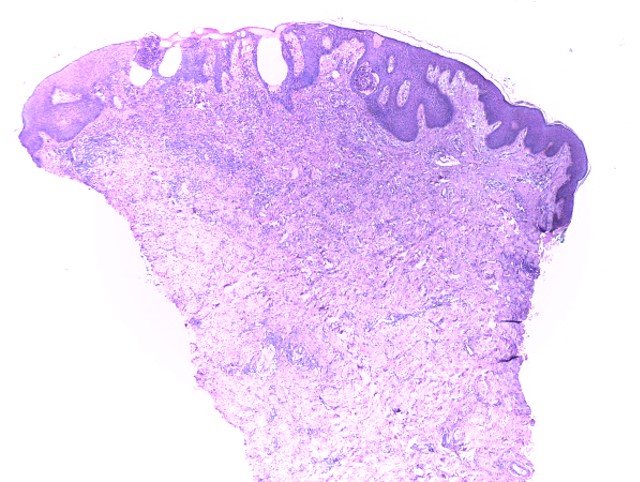

El pénfigo vegetante, es una variante rara del pénfigo vulgar (PV) corresponde a 1-2 % de los casos, las características clínicas e histopatológicas habitualmente permiten la diferenciación en 2 subtipos descritos: Neumann y Hallopeau, pero en ocasiones pueden presentarse de forma simultánea o secuencial. Las lesiones adoptan un aspecto vegetante afectando cualquier área de la piel, pero predomina en áreas intertriginosas y mucosa oral. Presentamos el caso de una paciente de 31 años de edad, con 1 año de evolución de placas eritematosas con vesículas y pústulas en la superficie cutánea, simulando dermatosis eccematosas que no permitían realizar el diagnóstico. Luego de la suspensión del tratamiento con esteroides sistémicos que recibía, se logró establecer el diagnóstico definitivo al evidenciar las características clínicas del pénfigo vegetante y corroborar con el estudio histológico e inmunofluorescencia directa.

Pemphigus vegetans, is a rare variant of pemphigus vulgaris (PV) corresponding to 1-2% of cases, clinical and histopathological characteristics usually allow the differentiation into 2 described subtypes: Neumann and Hallopeau, but sometimes they can present simultaneously or sequentially. Lesions adopt a vegetative appearance, affecting any area of the skin, but predominate in intertriginous areas and oral mucosa. We present the case of a 31-year-old female, who presented clinical manifestations of both variants, making their differentiation impossible, simulating eccematous dermatosis. After suspension of systemic steroids, final diagnosis was made based on clinical, histologic and direct immunofluorescence studies.